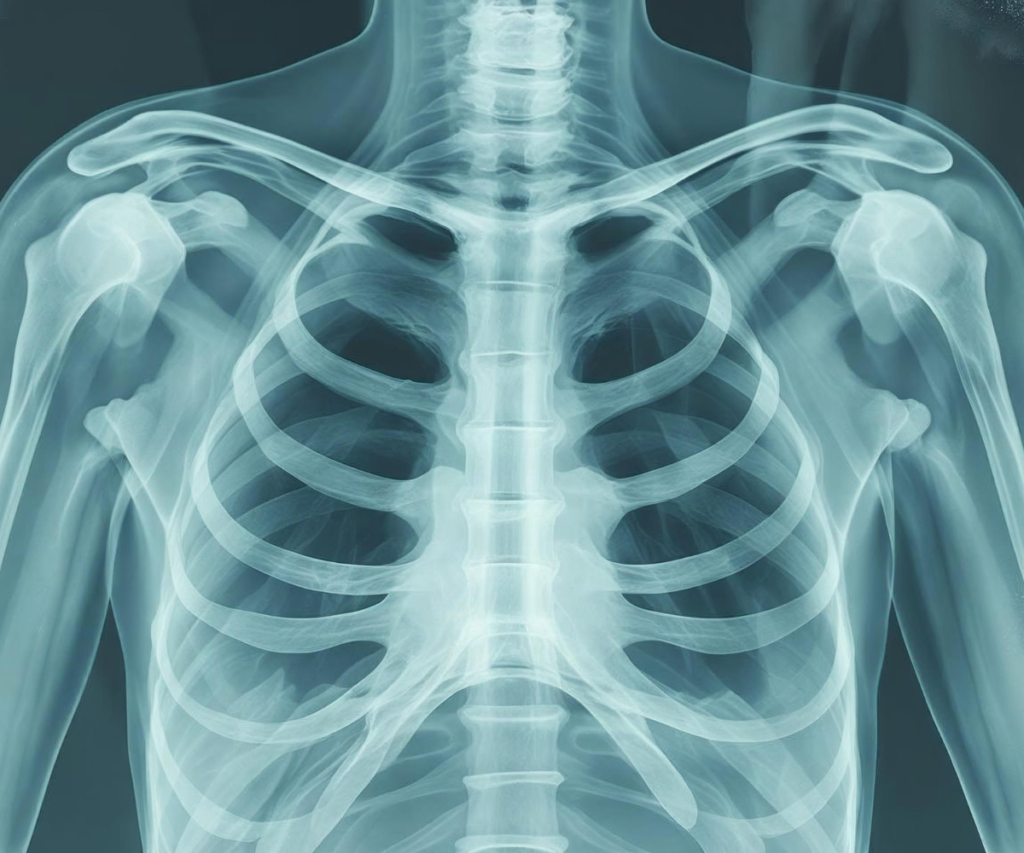

Understanding EVALI: What Happens to the Lungs

EVALI is a form of acute lung injury that occurs due to inhalation of harmful chemicals found in some vaping products. Symptoms can appear suddenly and range from mild respiratory discomfort to severe breathing difficulties requiring mechanical ventilation.

Medical experts warn that EVALI could represent just the tip of the iceberg, suggesting that chronic, long-term tissue damage may develop later in both smokers and vapers.

EVALI may be just an acute manifestation of lung injury, while the long-term consequences of vaping remain uncertain. Experts warn of potential risks including:

- Chronic lung disease